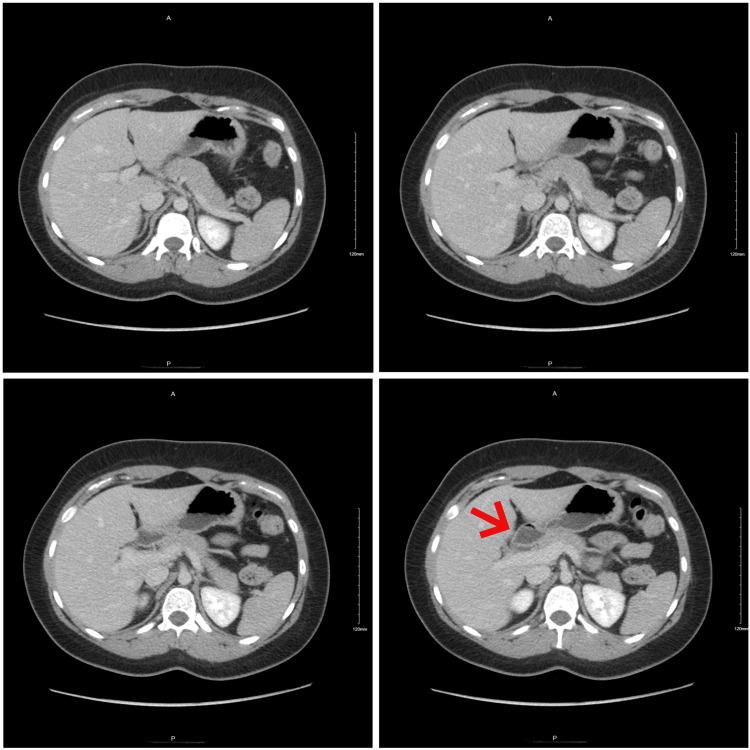

Gallbladder agenesis (GA) is a rare congenital malformation with less than 500 reported cases. Often an incidental finding intraoperatively or in postmortem autopsies, the first reported case dates back to 1701. We discuss the case of a 21-year-old female presenting with classic biliary symptoms who, on imaging, failed to have a visualizable gallbladder. Initial ultrasound (US) reported a non-visualized gallbladder with gallbladder contraction as a possible explanation. More advanced imaging allowed for the preoperative diagnosis, thus preventing an unpleasant intraoperative surprise. As imaging techniques continue to advance, unnecessary operations can hopefully be avoided, albeit a difficult diagnosis to make.

摘要

胆囊缺如(GA)是一种罕见的先天性畸形,报告病例不足500例。通常是在术中或尸检时偶然发现,首例报告病例可追溯到1701年。我们讨论了一名21岁女性的病例,该患者表现出典型的胆道症状,影像学检查未发现可视化胆囊。最初的超声(US)报告胆囊未显示,胆囊收缩可能是一种解释。更先进的影像学检查实现了术前诊断,从而避免了术中令人不快的意外情况。随着成像技术的不断进步,有望避免不必要的手术,尽管这是一个难以做出的诊断。